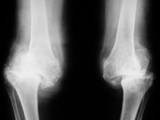

Charcot-knees

Charcot-knees